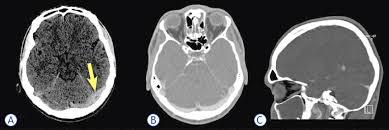

Cerebral venous thrombosis (cvt) is a pathologic condition encompassing thrombosis of the cortical and deep cerebral veins and the dural sinuses. Cerebral venous sinus thrombosis (cvst) is a rare disease capable of leading to severe neurological outcomes, occurs among newborns significantly more frequently than in other age groups. Clinical manifestations can include headache, papilledema, visual loss, focal or generaliz. Recommendations on the evaluation and management of cerebral venous thrombosis during pregnancy and in the pediatric population are provided. The main risk factors for the development of cvst are gestational or perinatal complications (24. Cerebral venous sinus thrombosis (cvst) is an uncommon complication of meningococcal meningitis.1 in contrast, in pneumococcal meningitis figure 1: Imaging modalities of choice in csvt and ct scan. What causes cerebral venous sinus thrombosis? Cerebral venous thrombosis (cvt) is an uncommon disorder in the general population. Cvst is an uncommon type of stroke. Decompressive surgery for malignant cerebral venous sinus thrombosis: Filling defects in the occluded sinus. Ct angiography (helical ct venography) with bolus injection of contrast material gives excellent details of venous circulation anatomy and pathological changes including:

Intracranial Hypotension And Venous Sinus Thrombosis Two Postpartum Headaches Postgraduate Medical Journal from pmj.bmj.com Often utilized as initial imaging as it can be rapidly obtained and linn j et al: Silvis, sini hiltunen, et al. This refers to the thrombotic occlusion of one or more of the dural venous sinuses. Cerebral venous sinus density on noncontrast ct correlates with hematocrit. Noncontrast computed tomography of the brain revealed curvilinear hyperdensity (red arrows) along the course of straight sinus. For the cerebral venous sinus thrombosis study group. Thrombosis of cerebral veins and venous sinuses is a rare disease, which accounts for less than 1% of all cases of stroke. This condition may also be called cerebral sinovenous thrombosis.

Cerebral venous sinus thrombosis occurs when a blood clot forms in the brain's venous sinuses. For the cerebral venous sinus thrombosis study group. Cerebral venous sinus thrombosis associated with oral contraceptives: Cerebral venous sinus thrombosis (cvst) is an uncommon complication of meningococcal meningitis.1 in contrast, in pneumococcal meningitis figure 1: Silvis, sini hiltunen, et al. Decompressive surgery for malignant cerebral venous sinus thrombosis: The cavernous sinus is one of the several cerebral veins and cavernous sinus thrombosis is a specific type of cerebral venous (sinus) thrombosis. Hanprasertpong t., hanprasertpong j., riabroi k. Cvst is a rare form of stroke. Cerebral venous thrombosis in the absence of headache. The mainstay of management is. The most frequent and often early symptom of thrombosis of cerebral veins and sinuses is a headache. Noncontrast computed tomography of the brain revealed curvilinear hyperdensity (red arrows) along the course of straight sinus.

Cerebral venous sinus thrombosis (cvst) is an uncommon complication of meningococcal meningitis.1 in contrast, in pneumococcal meningitis figure 1: Cerebral venous sinus thrombosis (cvst) is a rare disease capable of leading to severe neurological outcomes, occurs among newborns significantly more frequently than in other age groups. Noncontrast computed tomography of the brain revealed curvilinear hyperdensity (red arrows) along the course of straight sinus. Filling defects in the occluded sinus. Cerebral venous thrombosis (cvt) is an uncommon disorder in the general population.

Imaging Of Cerebral Venous Thrombosis Clinical Radiology from els-jbs-prod-cdn.jbs.elsevierhealth.com An unusual diagnosis and management of cerebral venous thrombosis: Cerebral venous sinus thrombosis as presenting feature of ulcerative colitis. Efns guideline on the treatment of cerebral venous and sinus thrombosis. Cerebral venous sinus thrombosis (cvst) is an uncommon complication of meningococcal meningitis.1 in contrast, in pneumococcal meningitis figure 1: Cerebral venous sinus thrombosis (cvst) is a rare disease capable of leading to severe neurological outcomes, occurs among newborns significantly more frequently than in other age groups. Residents and fellows contest rules | international ophthalmologists contest rules. Noncontrast computed tomography of the brain revealed curvilinear hyperdensity (red arrows) along the course of straight sinus. Thrombosis of cerebral veins and venous sinuses is a rare disease, which accounts for less than 1% of all cases of stroke.

Cerebral venous sinus thrombosis as presenting feature of ulcerative colitis. Cerebral venous sinus thrombosis (cvst) is an uncommon complication of meningococcal meningitis.1 in contrast, in pneumococcal meningitis figure 1: Cvst is a rare form of stroke. Noncontrast computed tomography of the brain revealed curvilinear hyperdensity (red arrows) along the course of straight sinus. Cerebral venous sinus density on noncontrast ct correlates with hematocrit. Silvis, sini hiltunen, et al. Cerebral venous sinus thrombosis (cvst) is the presence of a blood clot in the dural venous sinuses, which drain blood from the brain. Filling defects in the occluded sinus. Cerebral venous thrombosis (cvt) is an uncommon but serious disorder. Cvst is an uncommon type of stroke. The cavernous sinus is one of the several cerebral veins and cavernous sinus thrombosis is a specific type of cerebral venous (sinus) thrombosis. The most frequent and often early symptom of thrombosis of cerebral veins and sinuses is a headache. Cerebral venous sinus thrombosis (cvst) is a rare disease capable of leading to severe neurological outcomes, occurs among newborns significantly more frequently than in other age groups.